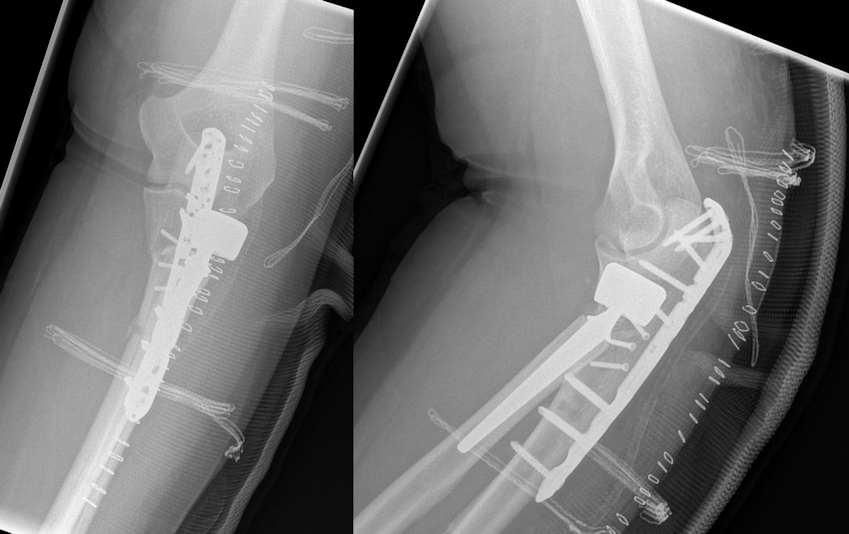

Osteosynthesis of the ulna was performed using a proximally contoured 3.5 mm LCP (locking compression plate) or precontoured 3.5 mm LCP Olecranon Plate (both Synthes GmbH, Umkirch, Germany) applied to the posterior surface of the ulna in dynamic compression mode (Figure 1 [Fig. 1], Figure 2 [Fig. 2], Figure 3 [Fig. 3]).

Figure 2: Postoperative radiographs. Osteosynthesis of the ulna was performed using a proximally precontoured olecranon plate applied to the posterior surface of the ulna. Implantation of a cemented bipolar radial head prosthesis.

Figure 3: Same patient 11 months after the injury: no degenerative changes and heterotopic ossifications. No signs of loosening of the radial head prosthesis. Good clinical outcome.